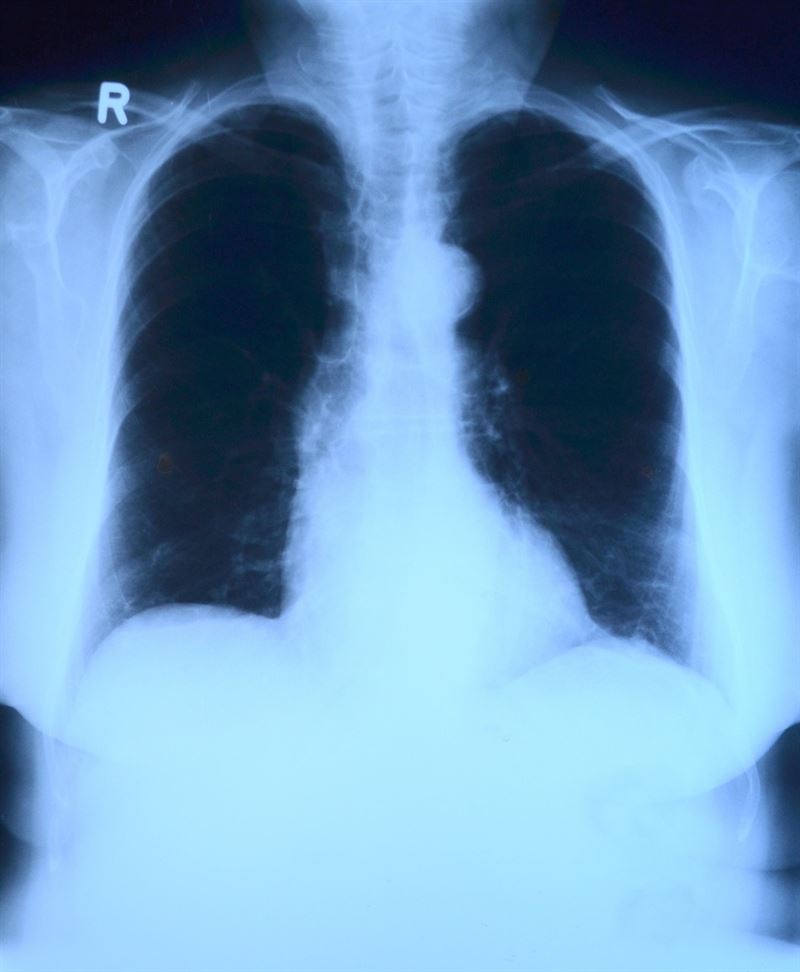

El cáncer de pulmón es el tumor que, año tras año, sigue registrando las peores cifras de mortalidad de todos los cánceres. «Cada año mueren 21.118 españoles a causa del cáncer de pulmón, un 82% hombres y un 17% mujeres. En total, esta cifra supone la suma de las muertes causadas por colon, mama y páncreas juntos», pone de relieve el doctor Mariano Provencio. Para los expertos del GECP es «esencial» poner el foco en este tumor, ya que las cifras que arroja en España son demoledoras.

«A nivel mundial este tumor aparece en 1,6 millones de personas cada año y deja tras de sí 1,3 millones de muertes. En nuestro país más de 400.000 personas han muerto por su causa en los últimos veinte años. Y para el futuro, estimamos que las cifras continúen en alza», destaca el doctor Provencio.